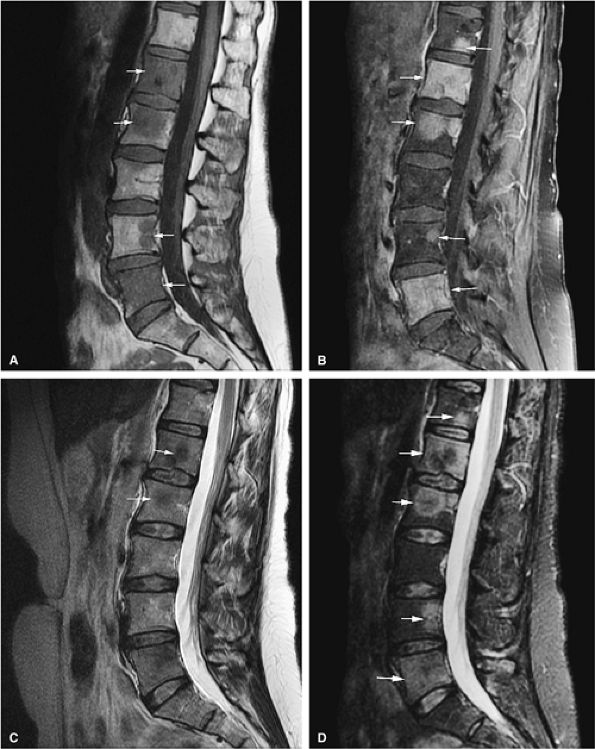

FIGURE 13.54 ● Prostate carcinoma that has metastasized to the spine. Spinal metastases (arrows) demonstrate low signal intensity on a T1-weighted sagittal image (A), with evidence of enhancement on a sagittal fat-suppressed T1-weighted image following the intravenous administration of gadolinium (B). The tumor is not well seen on the corresponding T2-weighted image (C) and is better visualized on the STIR sequence (D).